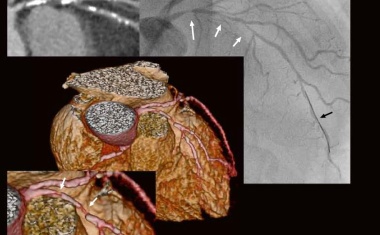

Ultraschnelle Herzbildgebung mit dem Low-Dose-Volumen-CT